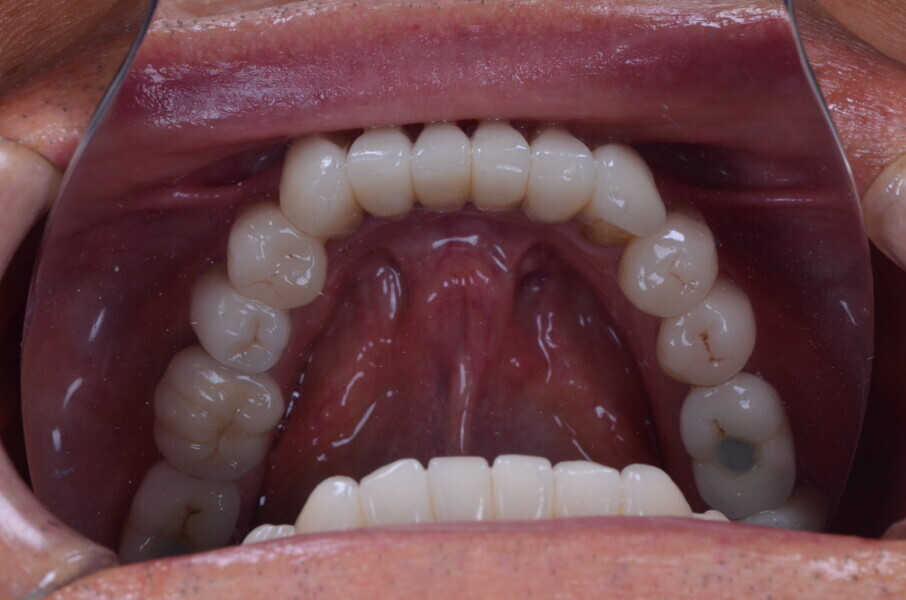

Figure 31 Occlusal view maxillary